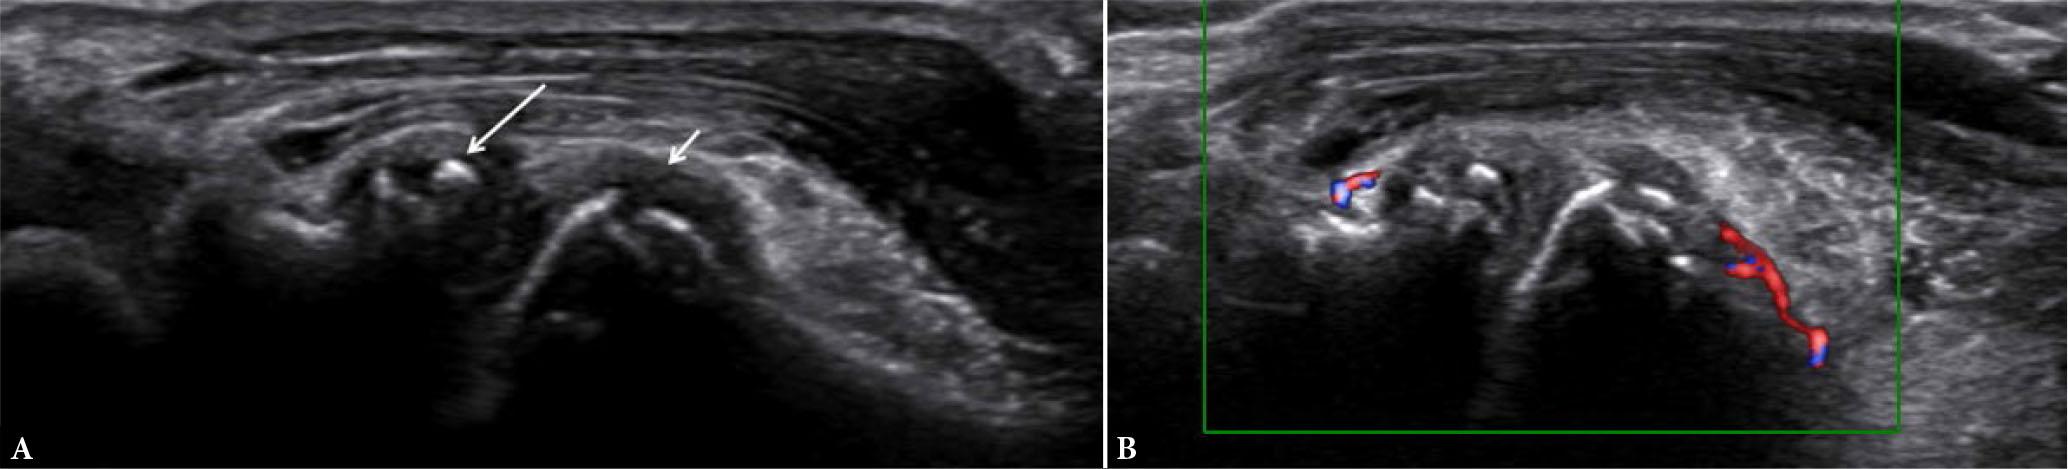

On US, tenosynovitis is defined as hypoechoic or anechoic thickened tissue, either with or without fluid within the tendon sheath, which is seen in two perpendicular planes and which may exhibit a Doppler signal(4) (Fig. 11). Tenosynovitis of the extensor carpi ulnaris (Fig. 12) is the most common, and represents an independent risk factor of erosive joint damage(10,20). A study by Ohrndorf et al.(11) found the specificity to detect tenosynovitis in grayscale and PD to be higher than the sensitivity.

Tenosynovitis. Long- (A) and short-axis (B,C) US images of the 2nd extensor compartment tendons at wrist joint show circumferential hypoechoicteno-synovial proliferation (arrows in A and B) with significant power Doppler signal (arrow in C) suggestive of active tenosynovitis, in a known case of RA

On MRI, tenosynovitis appears as peritendinous fluid with thickening and enhancement of the tendon sheath (Fig. 13).

Tenosynovitis. Axial proton density fat-suppressed images of different patients (A and B) show tenosynovial proliferation and edema of flexor (arrow in A) and extensor (arrow in B) tendons